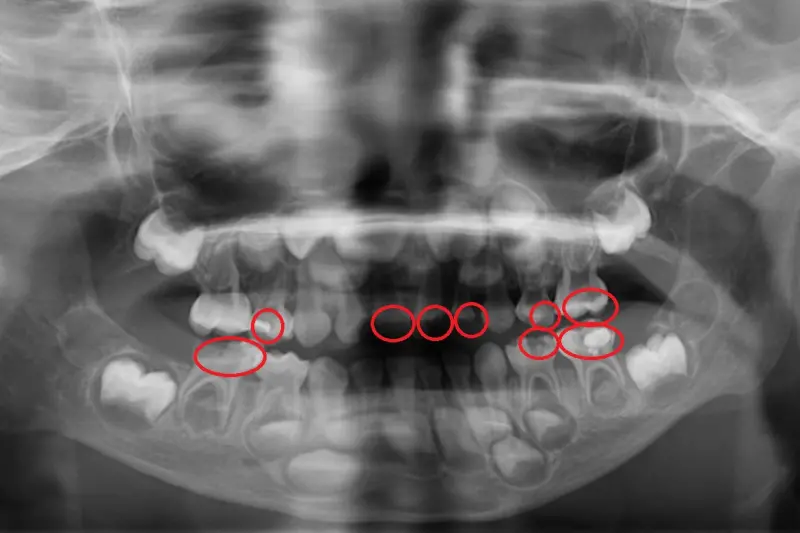

一名5歲男童在幼兒園定期接受塗氟與口腔檢查,最近卻在短時間內出現牙痛及臉頰腫脹,就醫後確診為乳牙嚴重蛀蝕併發蜂窩性組織炎,最終拔除4顆乳牙;醫師提醒,學校塗氟不能取代完整牙科檢查,延誤治療恐導致不可逆的損害。

台北慈濟醫院兒童牙科主治醫師陳默表示,乳牙齲齒的進展速度比恆牙快,且幼兒表達能力有限,往往牙齒已嚴重腐蝕或感染才發現;根據衛福部統計,齲齒盛行率在1~2歲為2.31%,3~4歲卻驟增至42.7%,與飲食習慣、清潔方式息息相關。